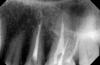

Z&Z Опубликовано 25 февраля, 2013 Поделиться Опубликовано 25 февраля, 2013 Добрый день, уважаемые стоматологи! Пожалуйста, оцените качество пломбировки каналов 2 зубов (2 канала и 4 канала) по прилагаемым снимкам.Каналы перепломбированы в связи с изначальной некачественной пломбировкой.Спасибо. Ссылка на комментарий

dok1 Опубликовано 25 февраля, 2013 Поделиться Опубликовано 25 февраля, 2013 Слишком сильно размыто. Вроде бы угадывается не большая недопломбировка. А что вас беспокоит? Ссылка на комментарий

Z&Z Опубликовано 25 февраля, 2013 Автор Поделиться Опубликовано 25 февраля, 2013 Слишком сильно размыто. Вроде бы угадывается не большая недопломбировка. А что вас беспокоит? Dok1, спасибо за Ваш ответ, беспокоит то, качественно ли сделано. Эти зубы под коронки. Ссылка на комментарий

dok1 Опубликовано 25 февраля, 2013 Поделиться Опубликовано 25 февраля, 2013 Нужны более чёткие снимки. Отвлечённо : иногда качество пломбировки диктуется каналами зубов - последствия предыдущего лечения. Не всегда всё во власти крайнего доктора. Ссылка на комментарий